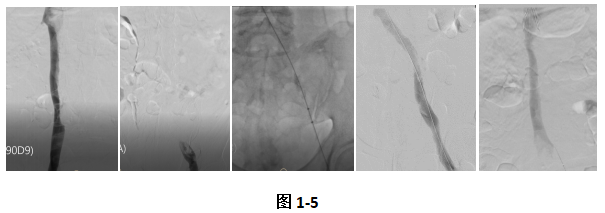

清华大学附属北京清华长庚医院是国内最早使用大腔血栓抽吸导管的医学中心之一,为静脉血栓患者治疗添加新的“兵器”。这款导管首次亮相就非常惊艳。患者张某某,因为突发的左腿肿胀就诊急诊科,行下肢静脉超声后发现左下肢深静脉血栓形成,进一步检查发现肾下下腔静脉、左侧肾静脉、左侧髂静脉都有血栓形成(图1、2),情况十分危急。血管外科团队急诊在滤器保护下采用Zelante导管进行左侧髂静脉及下腔静脉抽栓治疗(图3)。采用Zelante导管抽吸2分钟后可以看到左侧髂静脉及下腔静脉血栓基本完全清除,效果非常显著(图4、5),对于大腔血管血栓清除明显优于传统抽吸器械,患者术后恢复良好,腿肿完全消失,第三天就顺利出院。此后,血管外科连续治疗了两例下腔及髂静脉血栓患者,均取得安全满意的效果,最大程度缓解了患者症状。